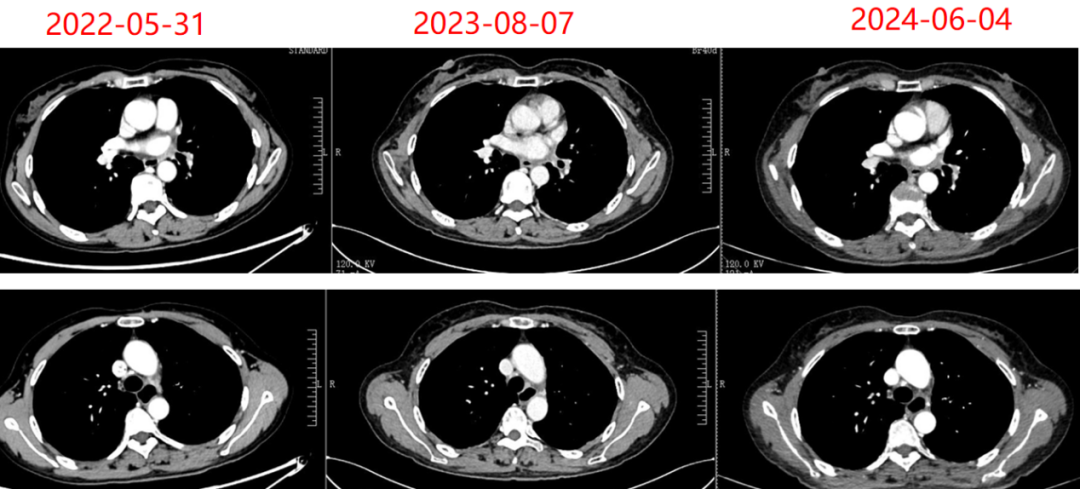

2020年12月11日行胸部增强CT:提示右肺门及右肺下叶占位,考虑恶性。右肺及左肺斜裂多发小结节,考虑转移。纵隔内及右肺门多发淋巴结增大,考虑转移。心包少量积液。左肺下叶小肺大疱。颈部、全腹CT平扫

加增强未见明显异常。

图4. 2020年12月11日CT检查

结果